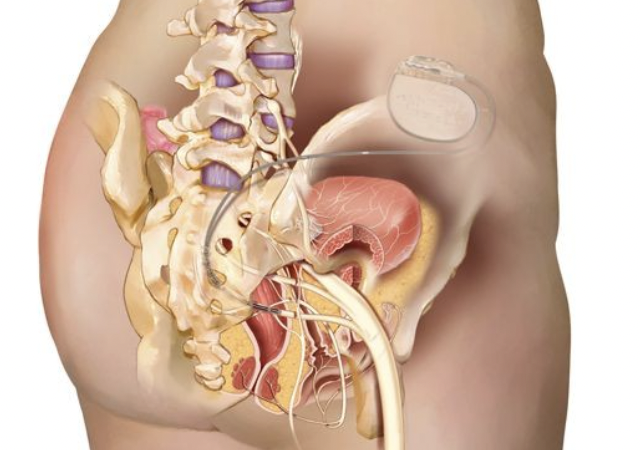

La neuromodulación se realiza mediante la implantación de un pequeño dispositivo que envía impulsos eléctricos suaves a los nervios sacros que controlan la vejiga y el intestino (Neuromodulación Sacra) o mediante la estimulación del nervio tibial en el tobillo (Estimulación del Nervio Tibial Posterior).